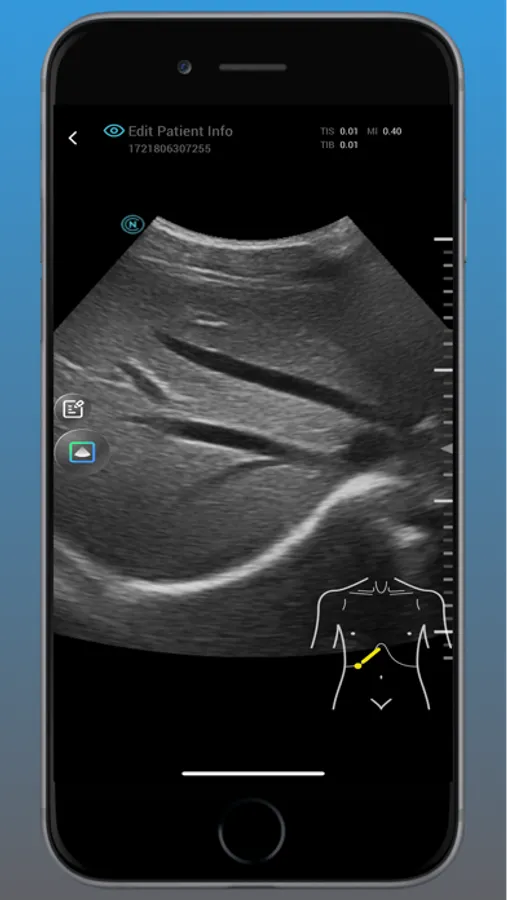

Neo Medical Ultrasound offers high imaging quality in real-time for physicians to improve daily patience care. Neo Medical app features different modes such as B Mode, Color Doppler, Pulsed Wave, and Motion mode. It is designed for medical professionals to easily access user interface to enhance portability and efficiency in daily workflows.

neo Medical Ultrasound System Screenshots